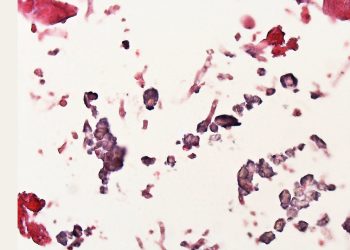

Diagnosis of Aspergillosis Diagnosis of aspergillosis involves evaluating...